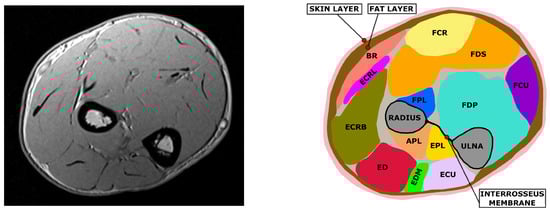

While the skin, fat and bones can be easily identified due to their different contrast in the T1-weighted MRI image, muscle tissue needs to be subdivided into the different muscles that compose it. The forearm contains about 20 muscles which are responsible for forearm pronation/supination, wrist radial/ulnar deviation and flexion/extension, and for finger flexion/extension. It is possible to roughly divide the forearm’s muscles into two groups based on their function: extensors along the posterior side and flexors on the anterior side. Additionally, extensor and flexors can be further divided into superficial and deep muscles depending on their positioning in the cross-section. Muscles delineate complex paths along the forearm. Cross sections at different longitudinal coordinate of the forearm can therefore be identified as different muscle sets. The segmentation process allows for the identification and definition of the muscle’s position, cross sectional areas, and boundaries (Figure 3).

For all subjects a single slice was selected. The selected slice contains for every subject the same set of muscles, which were identified using the imaging software ImageJ [22]. The considered set of muscles was the following: Abductor Pollicis Longus (APL), Extensor Pollicis Longus (EPL), Brachioradialis (BR), Extensor Digitorum (ED), Extensor Carpi Radialis Longus (ECRL), Extensor Carpi Radialis Brevis (ECRB), Extensor Carpi Ulnaris (ECU), Extensor Digiti Minimi (EDM), Flexor Digitorum Profundis (FDP), Flexor Digitorum Superficialis (FDS), Flexor Carpi Ulnaris (FCU), Flexor Carpi Radialis (FCR).

Figure 3. Example of segmentation on an MRI slice. On the left the original MRI is depicted, on the right its segmentation is reported. Muscles are represented with different colors, the radius and ulna bones are reported in gray. It is possible to observe the interosseus membrane connecting ulna and radius and dividing the posterior and the anterior side muscles. Skin and fat layers are colored respectively in pink and brown.